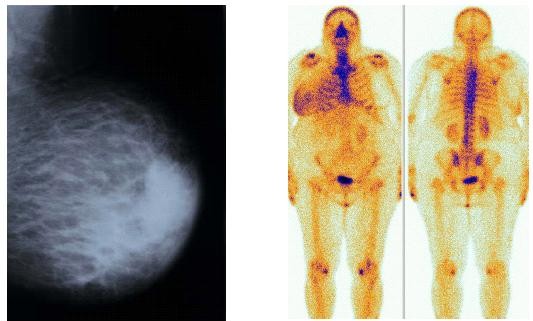

73-letá pacientka s lokálně pokročilým málo diferencovaným intraduktálním pravého prsu. T4N2MO. Při kontrolním mammologickém vyšetření má pacientka za sebou 6 serií chemoterapie. Probíhá hormonoterapie. Klinicky na rozhraní horních kvadrantů tuhá rezistence s infiltrací kůže bez fixace ke spodině, hojící se exulcerace na č.12 na bradavce. RTG: St dx.: Přetrvává cípaté zastínění vpravo 20X35mm s mikrokalcifikacemi. UZ vyšetření: Na rozhraní HQ je nehomogenní nepravidelné zastínění o průměru 25mm. Patologicky změněné uzliny v axile dx, jsou menší. Podklíčková i nadklíčková oblast bez lymfadenopatie.

Výsledky : U první nemocné je patrno ložiskové zvýšení akumulace radiofarmaka v tumorózní tkáni pravého prsu s kalcifikacemi. Plošné zvýšení záchytu aktivity v okolí odpovídá kolaterálnímu edému. U druhé nemocné se zobrazuje výrazné zvýšení akumulace v jizevnatě změněné kůži i podkoží levého prsu a jeho stagnace v edému, dále vazba na skupinu mikrokalcifikací centrálně a dorzálně. Ložisko zvýšené akumulace v pravém prsu odpovídá kožní metastáze.

Scintigrafie skeletu je u diagnózy nádorové choroby prsu součástí stanovení stadia nemoci. Mechanismus vazby osteotropního radiofarmaka v kosti není přesně znám. Zčásti se váže na krystaly hydroxyapatitu, zčásti na mezibuněčnou hmotu bílkovinné povahy. Aktivita radiofarmaka se v karcinomu prsu vázala na kalcifikace v tumorózní tkáni, prokázala svou afinitu ke kalciu v jizvící se tkáni prsu i v nekroticky změněné kožní metastáze.

Pacientka s karcinomem pravého prsu